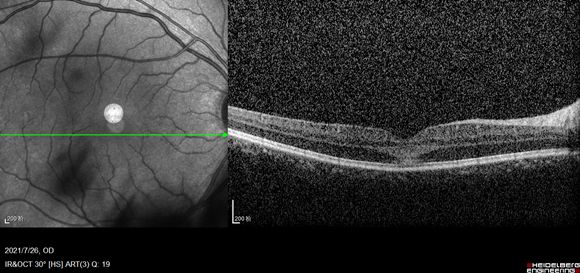

听完患者的讲述,我又给他做了检查,发现患者的右眼球内异物比较大,而且将视盘鼻侧的视网膜扎穿。由于球内异物在眼睛里的时间比较长,黄斑区也受到了累及,如果再发生感染的话,视力会受到不可逆影响。

右眼视力0.25 视乳头鼻侧见一片状铁锈色异物嵌入